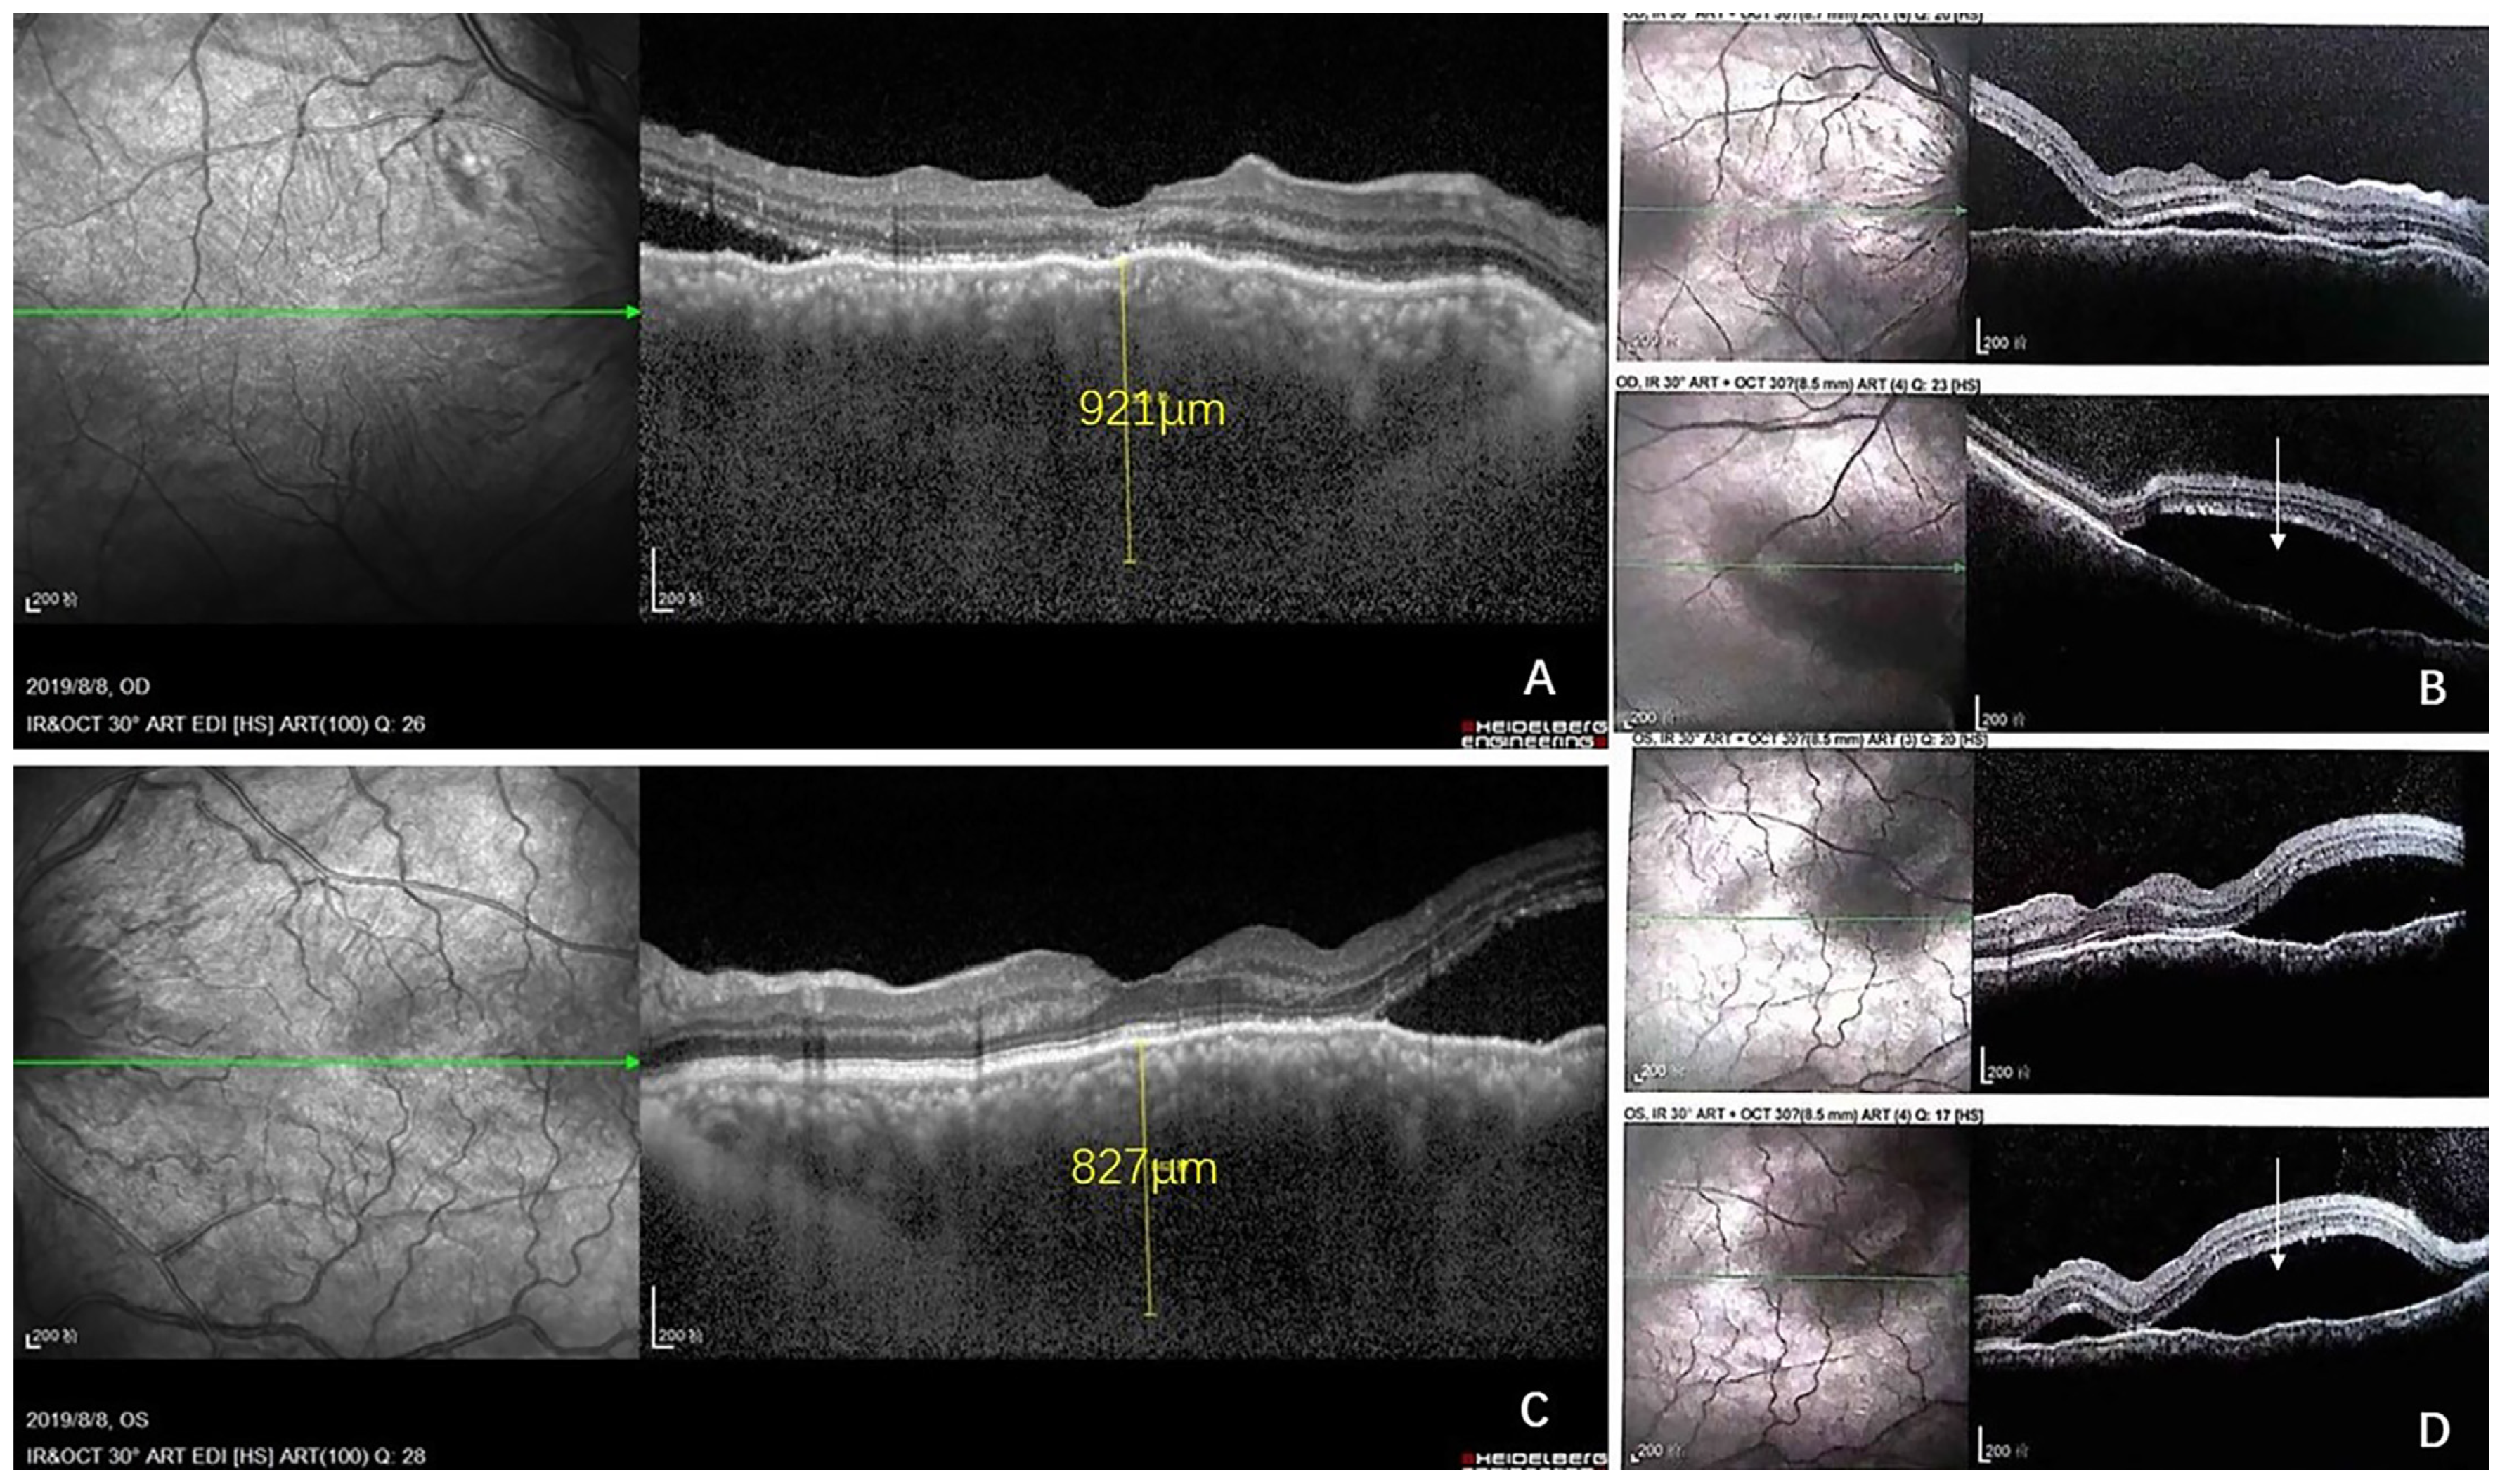

2. Case Report

- Shields, C.L.; Arepalli, S.; Pellegrini, M.; Mashayekhi, A.; Shields, J.A. Choroidal lymphoma shows calm, rippled, or undulating topography on enhanced depth imaging optical coherence tomography in 14 eyes. Retina 2014, 34, 1347–1353. [Google Scholar] [CrossRef]